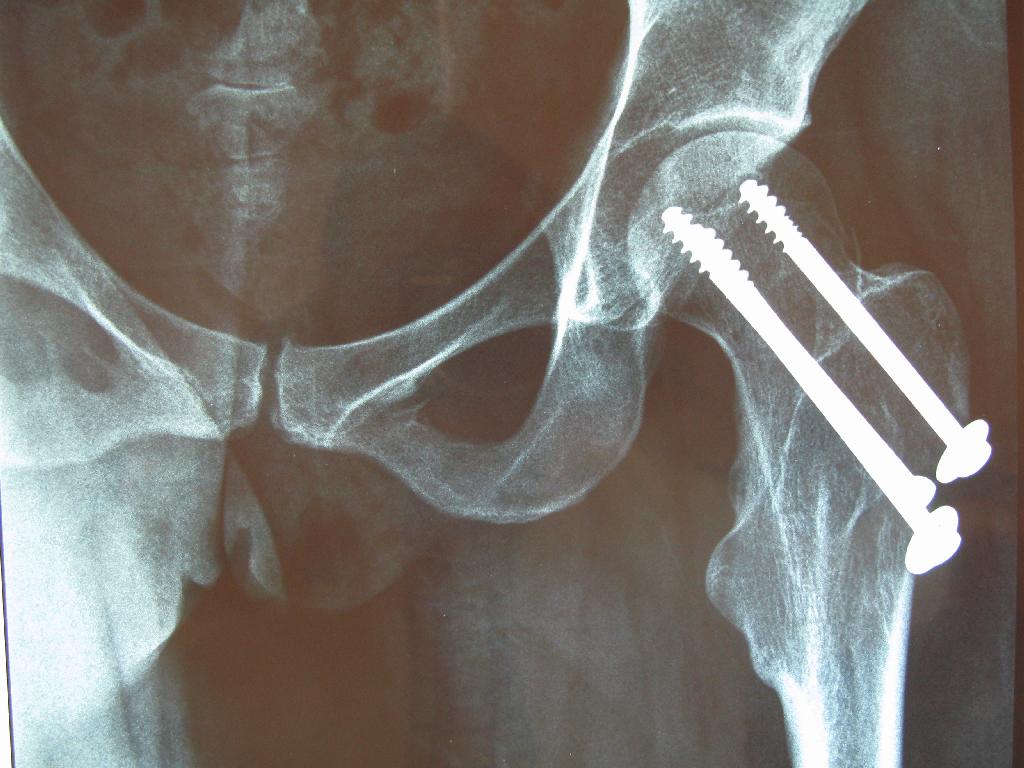

CADERA1